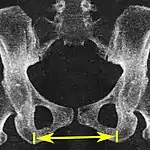

| Intertuberous diameter | ![]() |

![]() Axial plane |

The closest bony points of the ischial tuberosities | 10 to 12 cm.[6] | |